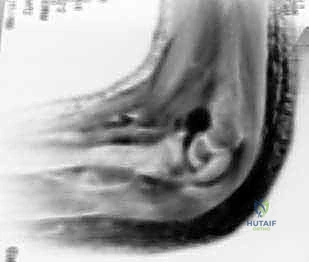

Standard radiographic evaluation must include true anteroposterior (AP), lateral, and internal oblique views of the elbow. The internal oblique view is particularly critical, as it profiles the lateral condyle and often reveals the maximum extent of displacement that may be obscured on standard AP and lateral projections. If the degree of displacement is equivocal (hovering around the 2 mm mark), advanced imaging or dynamic assessment is required.

While Magnetic Resonance Imaging (MRI) can definitively assess the integrity of the cartilaginous hinge, it is cumbersome, expensive, and often requires general anesthesia in pediatric patients. Therefore, the gold standard for equivocal cases is an intraoperative arthrogram combined with a dynamic stress examination under fluoroscopy. By injecting radiopaque dye into the joint, the surgeon can directly visualize whether the articular cartilage is breached. If the dye leaks through the fracture site, or if the fragment displaces under gentle varus stress, the fracture is deemed unstable and mandates fixation.

Clinical & Radiographic Imaging Archive